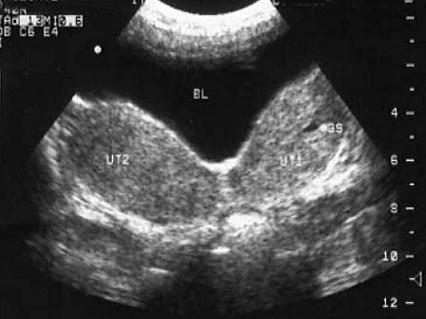

超声检查如图,较完整的诊断是 ( )A、子宫发育不良B、宫腔积液C、双子宫D、双子宫并一侧妊娠E、双角子宫

选项 A、子宫发育不良 B、宫腔积液 C、双子宫 D、双子宫并一侧妊娠 E、双角子宫

答案 D